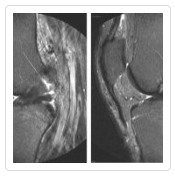

Traditionally, doctors have waited to perform ACL reconstruction for younger athletes until the patients have stopped growing. During ACL surgery, doctors drill tunnels through the tibia and femur. For younger patients whose growth plates may still be open, experts worried that damage could occur as a result of the drilling process. However, new technology is making it easier for orthopedic surgeons like Dr. Eric Millstein to treat ACL injuries in younger athletes. The 3-D MRI lets doctors plan out their ACL procedures with increased precision before the operation. This technology helps doctors reconstruct the ACL in younger patients without disturbing the growth plate, thereby allowing some athlete to return to play sooner.ACL surgery is not right for everyone, and some patients may benefit from physical therapy or bracing the knee. However, for